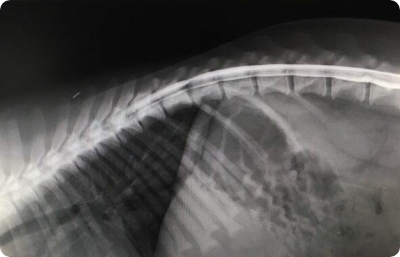

CT(コンピューター断層撮影)は、体の内部を輪切り状に撮影し、骨・内臓・血管などを立体的に確認できる画像検査です。

レントゲンやエコーではわかりにくい部分も、より詳しい情報が得られる場合があり、病気の早期発見や診療の判断材料として活用されます。

当院で導入予定の機器は16列マルチスライスCTで、一度に広範囲を撮影できるため、従来よりも短時間で検査が可能です。被ばく低減技術を搭載しており、低線量でも高精細(最小スライス厚0.625mm)の画像が得られます。撮影画像からは、任意の角度の断面像や3次元表示画像の作成も可能で、より詳細な検査が期待できます。